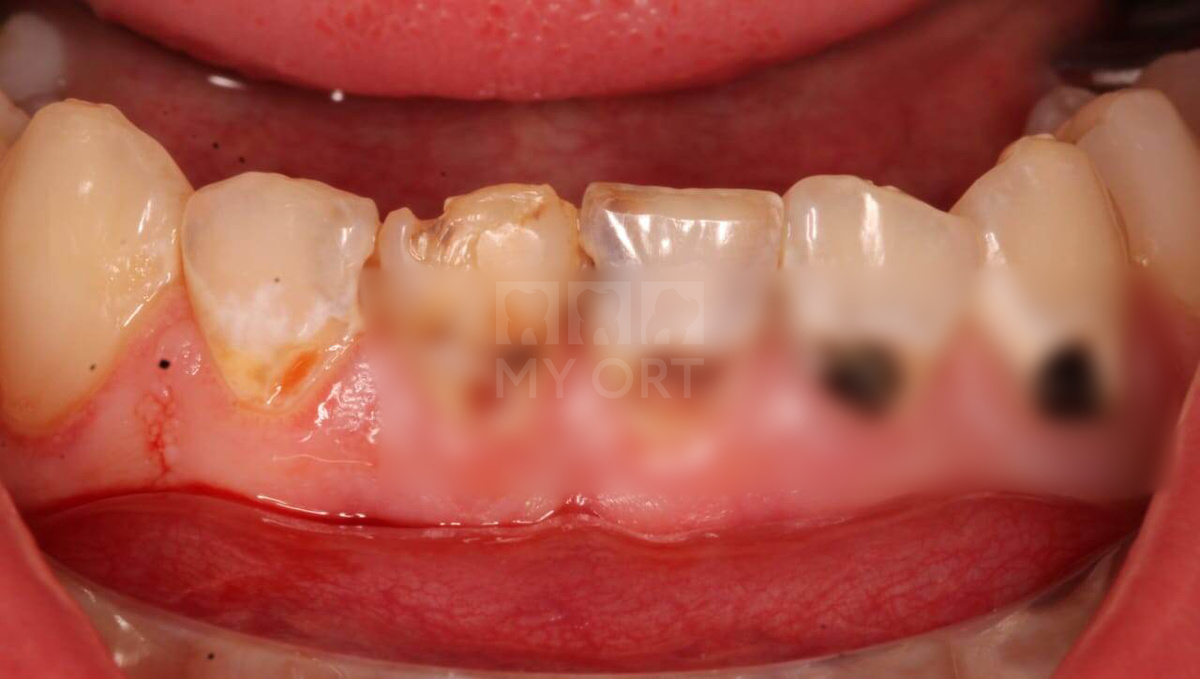

Ситуация ДО

На консультации пациент рассказал, что помимо эстетического дискомфорта во время общения и улыбки, он ощущал дискомфорт при приеме пищи и питья (беспокоила реакция на горячее/холодное, на сладкое, а также забивалась еда).

Пациент плохо следил за гигиеной зубов, поэтому у него образовались такие большие кариозные полости.